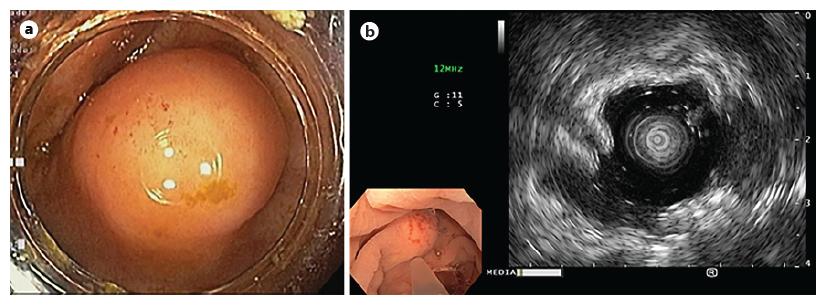

A 44-year-old female patient was subjected to total colonoscopy that revealed a 15 mm bulge in the cecum, covered by normal mucosa, compatible with subepithelial lesion, of hard consistency and no pillow sign (Fig. 1a). The lesion was evaluated by ultrasonography with mini-probe (Fig. 1b), which confirmed the presence of a sub-epithelial nodular hypoechoic lesion although it was not possible to safely distinguish between the second and third ultrasonographic wall layers.

Fig. 1. Endoscopic findings. a In the cecum, a 15 mm bulge with normal mucosa was observed. b Ultrasonography - a subepithelial nodular lesion was confirmed, although it was not possible to safely distinguish between the second and third ultrasonographic wall layers.